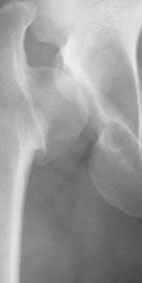

Pic. 1-5 preop plan; 6-8 similar case